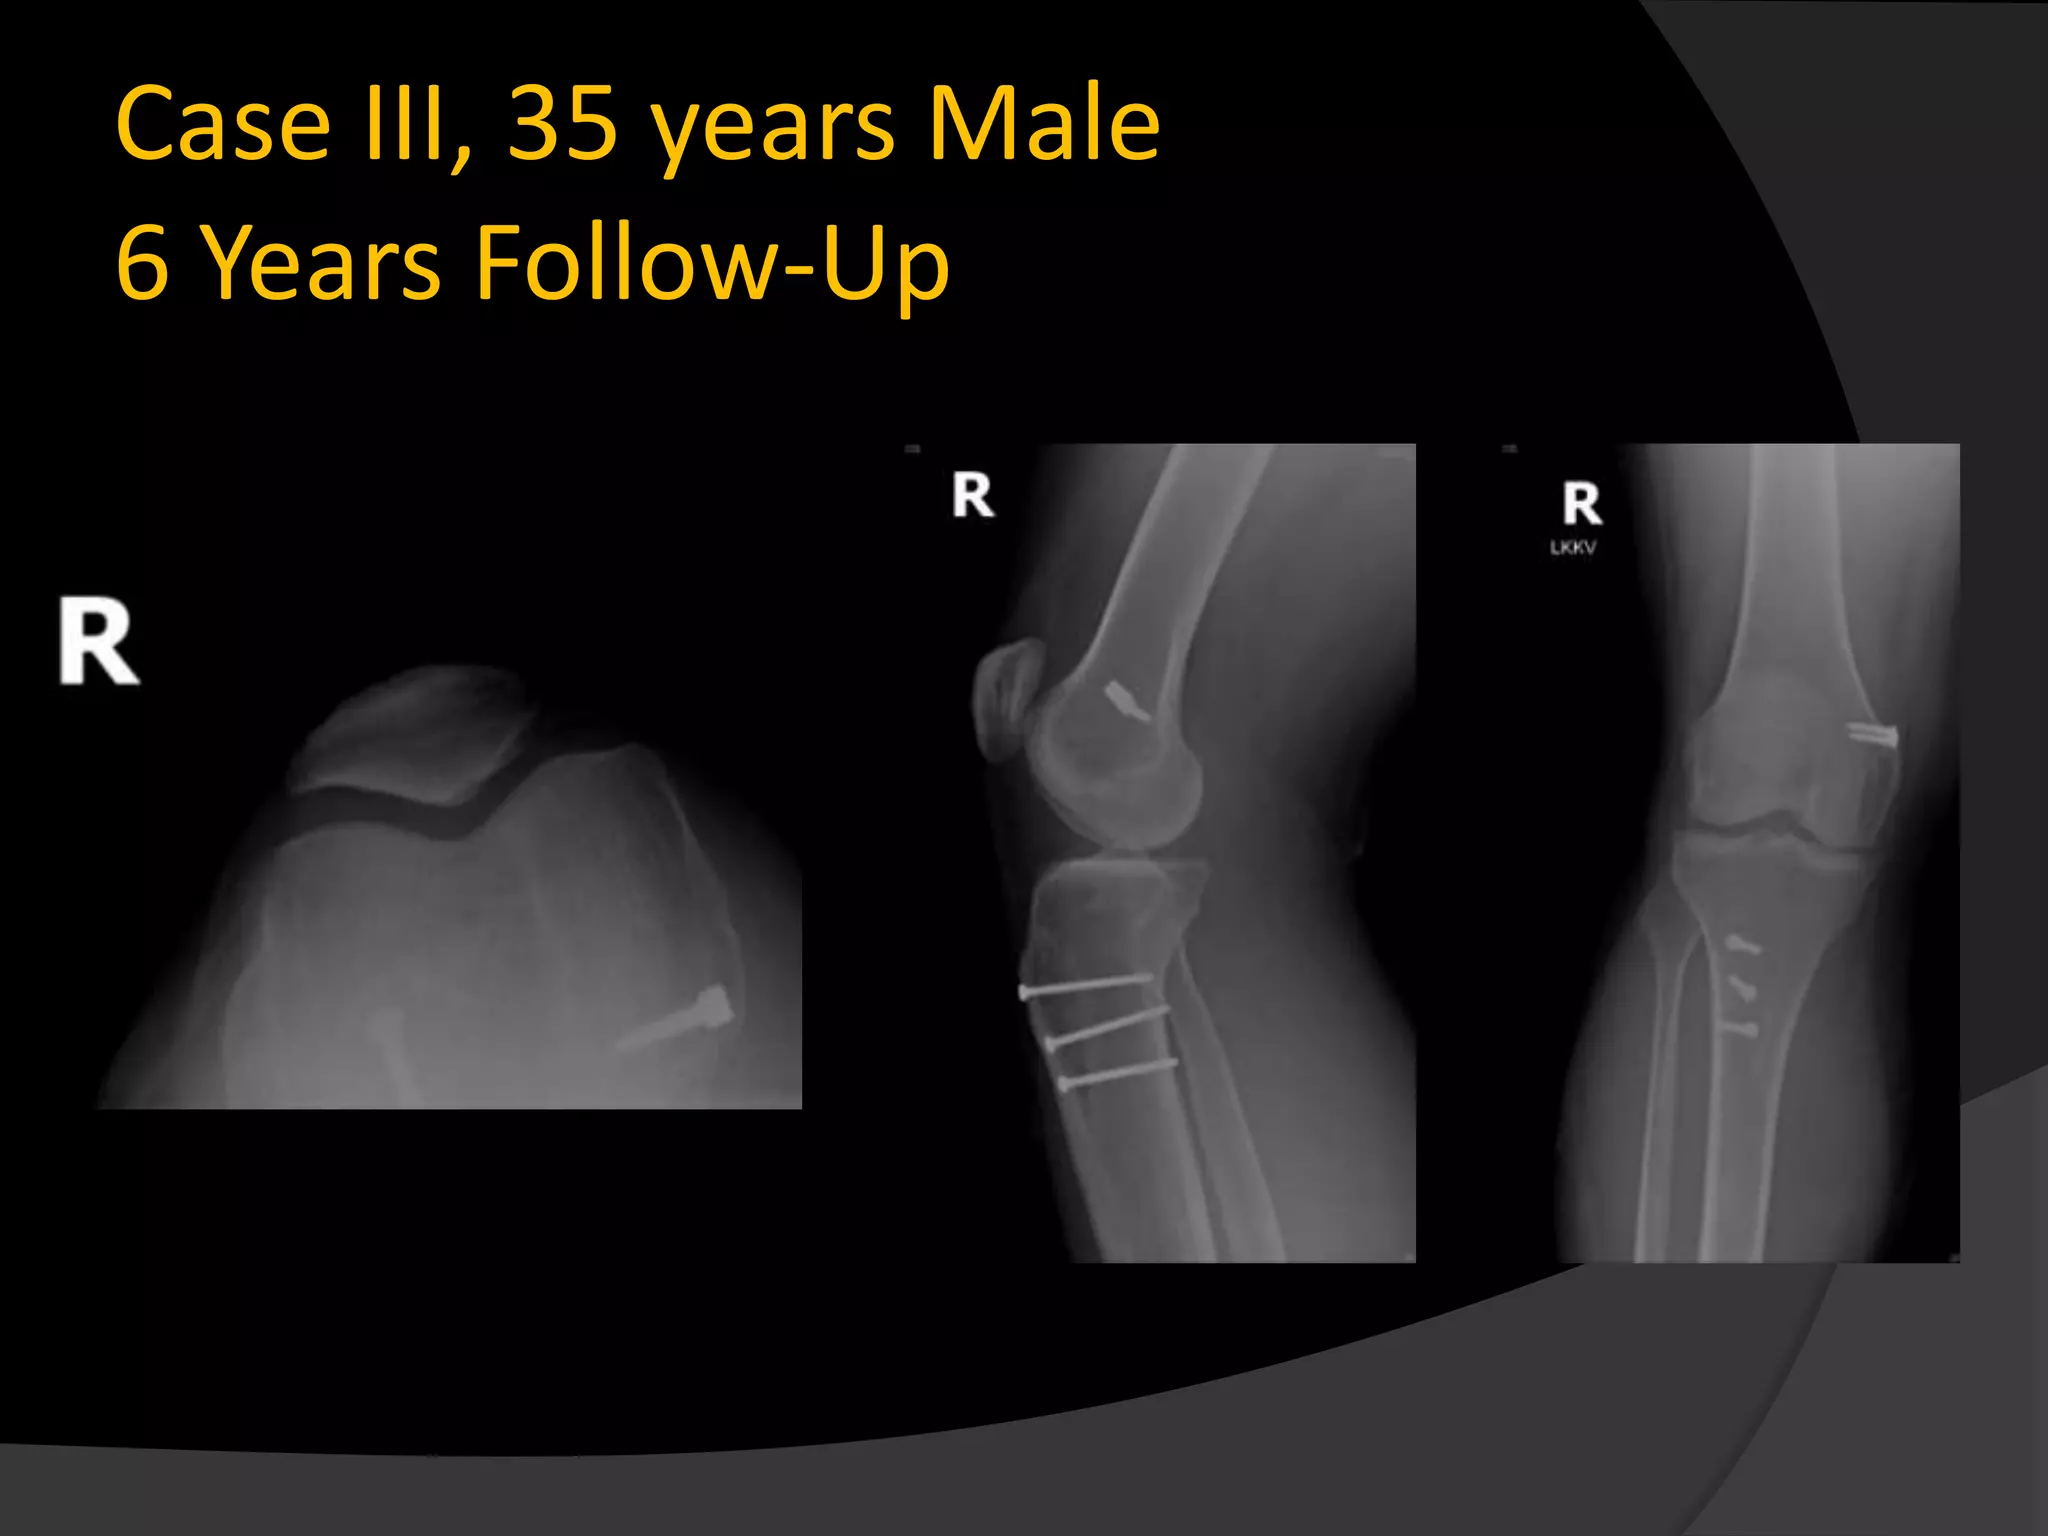

Case III, 35 years Male

6 Years Follow-Up

Case III, 35years Male 6 Years Follow-Up